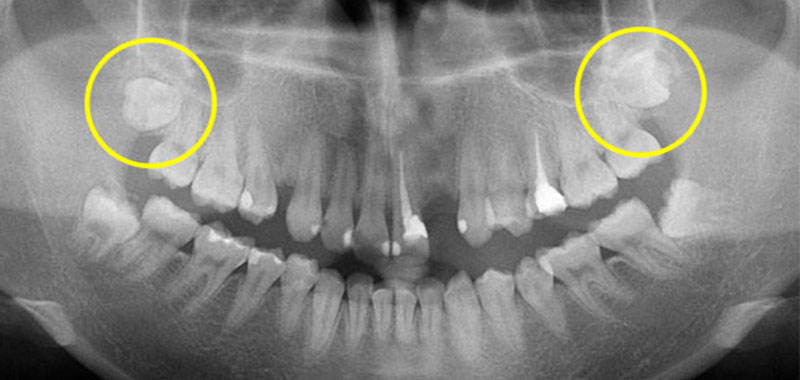

高高卡在上顎的智齒,這樣的智齒如果沒有症狀不一定要拔